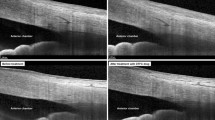

The Schlemm’s canal (SC) and the trabecular meshwork (TM) morphology manifestation in each age group. a A 8-year-old female subject. b A 34-year-old female subject. c A 48-year-old female subject. d A 75-year-old female subject. From (a to d) with aging, the SC diameter and area became smaller, and TM thickness increased

In the children’s group (7–14 years), SC was observable in 100% of the sections, which was significantly higher than in the other groups: 95.1% in group B (21–39 years), 88.3% in group C (40–59 years), and 80.6% in group D (60–83 years). In all individuals with SC visibility, the SC diameter varied from 50.8 μm to 393.5 μm in the different quadrants of the eye and the SC area ranged from 835.3 μm 2 to 17,727.1 μm2. When compiled according to the four age categories, the greatest diameter was measured in the children’s group (Fig. 2a); a clear decline in the mean SC diameter in the four quadrants was evident with age, and the linear correlation analysis indicated a significant age-dependent tendency (P < 0.001) (Table 2a, Fig. 2). We also demonstrated that age had the same effects on the SC area (Table 2b, Fig. 2). The changes in SC showed significant correlations with AL and ACD (P < 0.001), while other factors such as CCT and IOP did not vary with any SC parameter (P > 0.05). Quadrant comparisons indicated that both the SC diameter and area were wider in the nasal and temporal quadrants compared with the inferior and superior quadrants (Fig. 3) (P < 0.001).